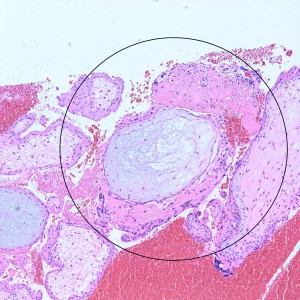

However, in one field we see a well-circumscribed nodule that, on low power, is very pink and glassy appearing, with large cells admixed.

On higher power, we can see that this nodule is mostly composed of this pink amorphous material with interspersed large, round cells with abundant eosinophilic and sometimes clear cytoplasm (arrows). There are essentially no mitoses and atypia is not very prominent.

On higher power of the acellular areas we can see vague outlines of the cells that may have been there and have now degenerated into this hyalinized stroma (black arrows). The cells that remain are large, round to oval, with dense eosinophilic to clear cytoplasm (red arrows).